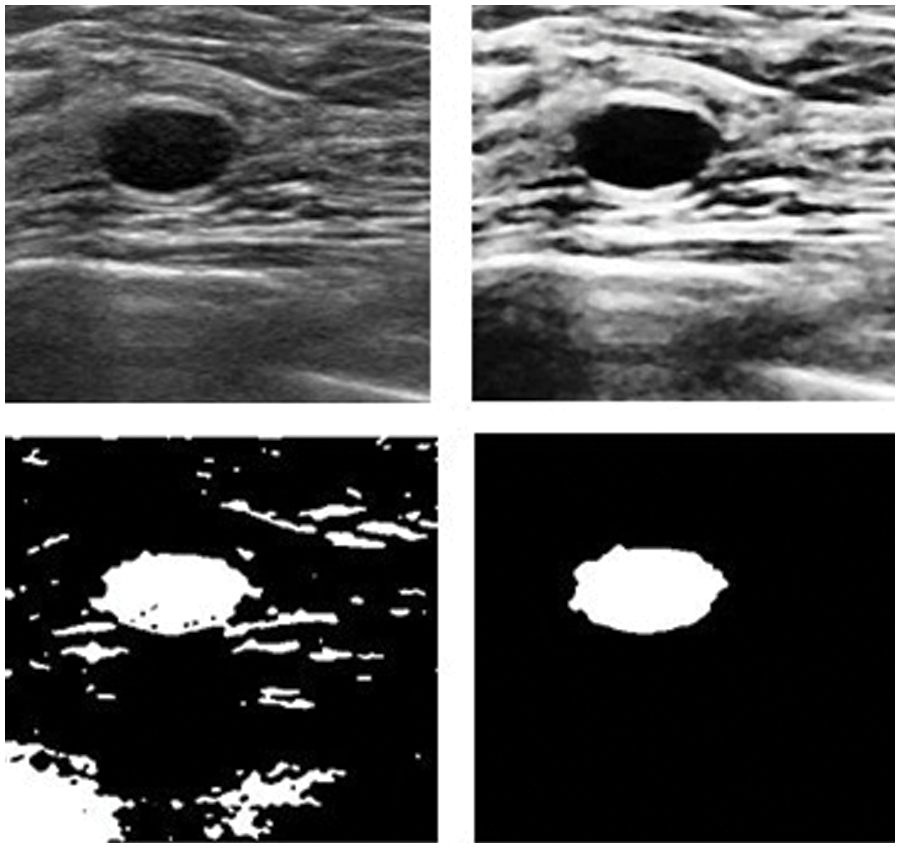

In this subsection, the framework shows the results after using U-Net architecture to segment the image after the process of denoising the image in the previous step. The U-Net model uses the result from the previous step after comparing the images of the five models and the level of noise. Tabs. 3 and 4 show the results after and before denoising the dataset of ultrasound, the results shows the enhancement of different metrics in the segmentation process after denoising the images, and the results also show the quality of u-net against the other methods, Fig. 10 shows the results of using U-Net in the segmentation process. The figure shows the ultrasound, mask, and predicted result using U-Net. Tabs. 5 and 6 show the results of classification of the segmented image into the malignant, tumor, and normal using different methods before and after removing noise, the results show the efficiency of methods after removing noise from images, and the results also show the efficiency of CNN against models. Fig. 11 shows the results of classifying the output into benign and malignant classes and Fig. 12 shows the results of removing noise in the enhancement stage.

Figure 12: Results after and before removing noise